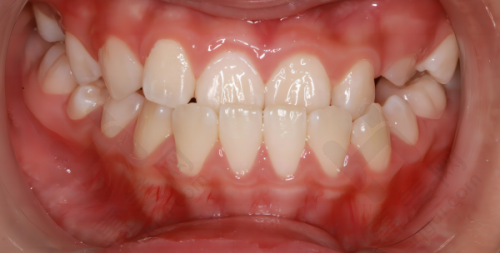

牙齿矫正项目也特别出色,能做全同步带状弓矫正、时代天使隐形矫正、儿牙时代天使早期矫正等项目,大人小孩都可以同时来进行矫正。除此之外,还有全瓷牙冠、牙齿瓷贴面、洗牙、补牙、儿童牙齿涂氟、牙周护理(超声洁牙 + 抛光套餐98元,清除茶渍烟渍)、残根接续、烤瓷牙、根管治疗、牙齿美白、地包天治疗、活动义齿等其他项目。